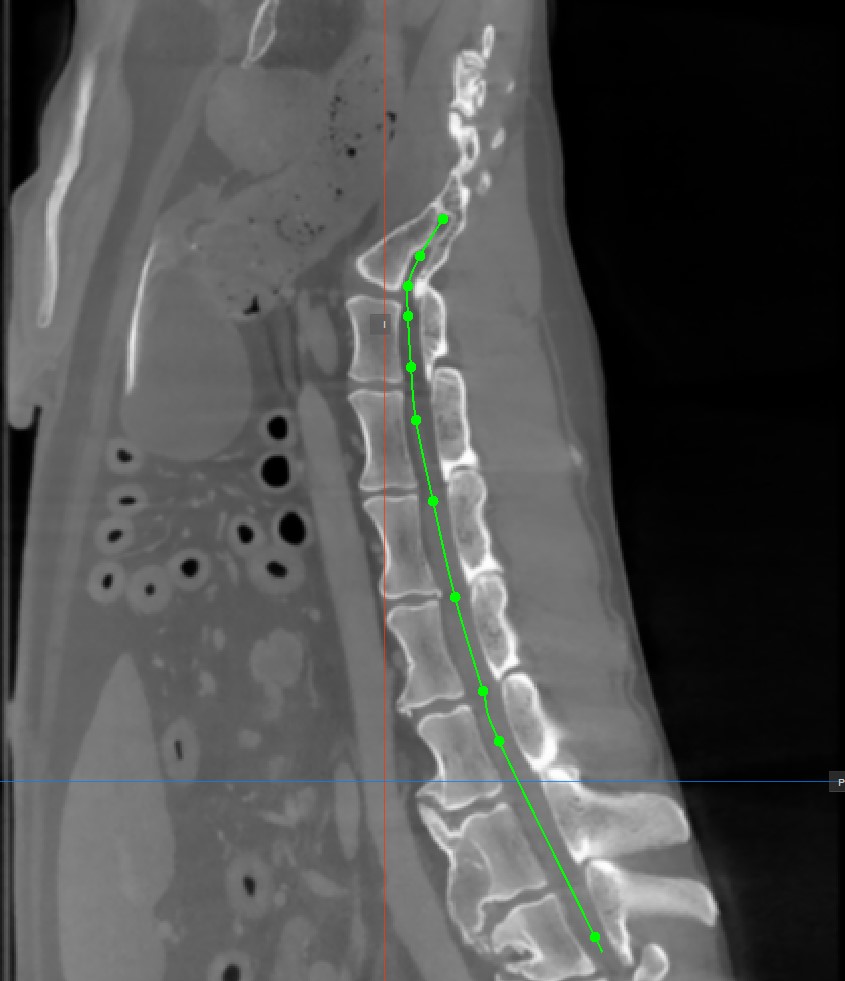

Um den Pfad abzuschließen, aktivieren Sie das Werkzeug

CMPR-Punkt hinzufügenerneut oder doppelklicken Sie mit der Maus auf das Bild, nachdem der letzte Punkt des Pfades gesetzt wurde. Der Pfad wird nach der Fertigstellung grün markiert.